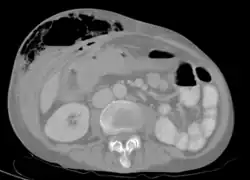

Abdominal CT scan with right colocutaneous fistula and associated subcutaneous pneumatosis

In anatomy, a fistula (pl.: fistulas or fistulae /-li, -l/; from Latin fistula, "tube, pipe") is an abnormal connection (i.e. tube) joining two hollow spaces (technically, two epithelialized surfaces), such as blood vessels, intestines, or other hollow organs to each other, often resulting in an abnormal flow of fluid from one space to the other.[2][3][4] An anal fistula connects the anal canal to the perianal skin. An anovaginal or rectovaginal fistula is a hole joining the anus or rectum to the vagina. A colovaginal fistula joins the space in the colon to that in the vagina. A urinary tract fistula is an abnormal opening in the urinary tract or an abnormal connection between the urinary tract and another organ. An abnormal communication (i.e. hole or tube) between the bladder and the uterus is called a vesicouterine fistula, while if it is between the bladder and the vagina it is known as a vesicovaginal fistula, and if between the urethra and the vagina: a urethrovaginal fistula. When occurring between two parts of the intestine, it is known as an enteroenteral fistula, between the small intestine and the skin it is known as an enterocutaneous fistula, and between the colon and the skin as a colocutaneous fistula.[3]

Types of fistula can be described by their location. Anal fistulas connect between the epithelialized surface of the anal canal and the perianal skin. Anovaginal or rectovaginal fistulas occur when a hole develops between the anus or rectum and the vagina. Colovaginal fistulas occur between the colon and the vagina. Urinary tract fistulas are abnormal openings within the urinary tract or an abnormal connection between the urinary tract and another organ such as between the bladder and the uterus in a vesicouterine fistula, between the bladder and the vagina in a vesicovaginal fistula, and between the urethra and the vagina in urethrovaginal fistula. When occurring between two parts of the intestine, it is known as an enteroenteral fistula, between the small intestine and the skin as an enterocutaneous fistula, and between the small intestine and the colon as a colocutaneous fistula.[3]